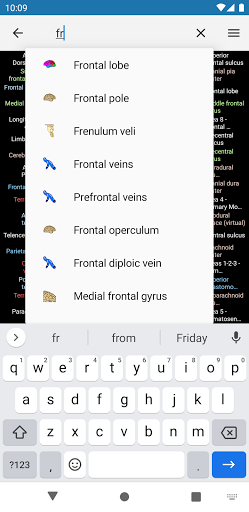

* تحسين أداء البحث عن البنية التشريحية

* اعثر على الأجزاء التشريحية الخاصة بك بسهولة أكبر بفضل ميزة البحث الجديدة والأكثر سهولة وقوة